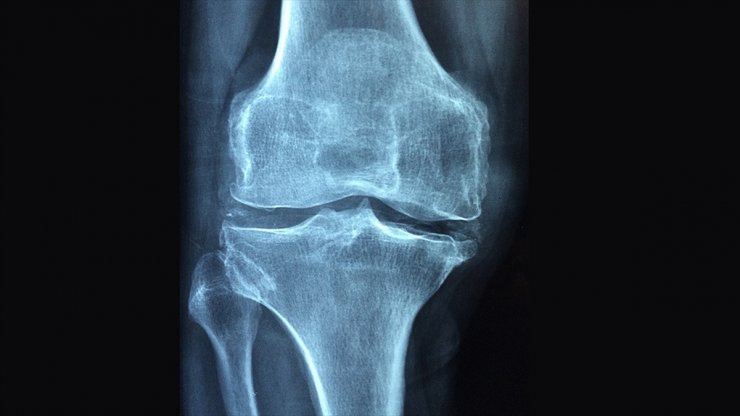

Osteoporoz Tüm Dünyada 3 Kadından Birini Kıskaca Alıyor

osteoporoz tüm dünyada 3 bayandan, 50 yaş üzerindeki 5 erkekten birini etkileyen bir sorun olduğunu, hastalığın kırık olmadığı sürece ağrı yapmadığı için sessiz ve sinsi ilerlediği söylendi.

Osteoporoz, tüm dünyada 3 bayandan birini ve 50 yaş üzerindeki 5 erkekten birini etkileyen global bir sorunudur." diyen Kutsal, "Osteoporoz, tüm dünyada 200 milyon bayanı etkiliyor.

60-70 yaşlarındaki bayanların üçte biri, 80 yaşlarındaki bayanların üçte ikisi bu hastalıktan etkileniyor.

50 yaşın üzerindeki bayanların yüzde 30'unda en az bir kırık bulunuyor. Dünyada her sene 1,5 milyon kalça kırığı oluşuyor. Yaşlanan popülasyon sebebiyle artması bekleniyor.

Osteoporoz, kırık olmadığı sürece ağrı yapmadığı için sessiz ve sinsi ilerleyen bir hastalık.